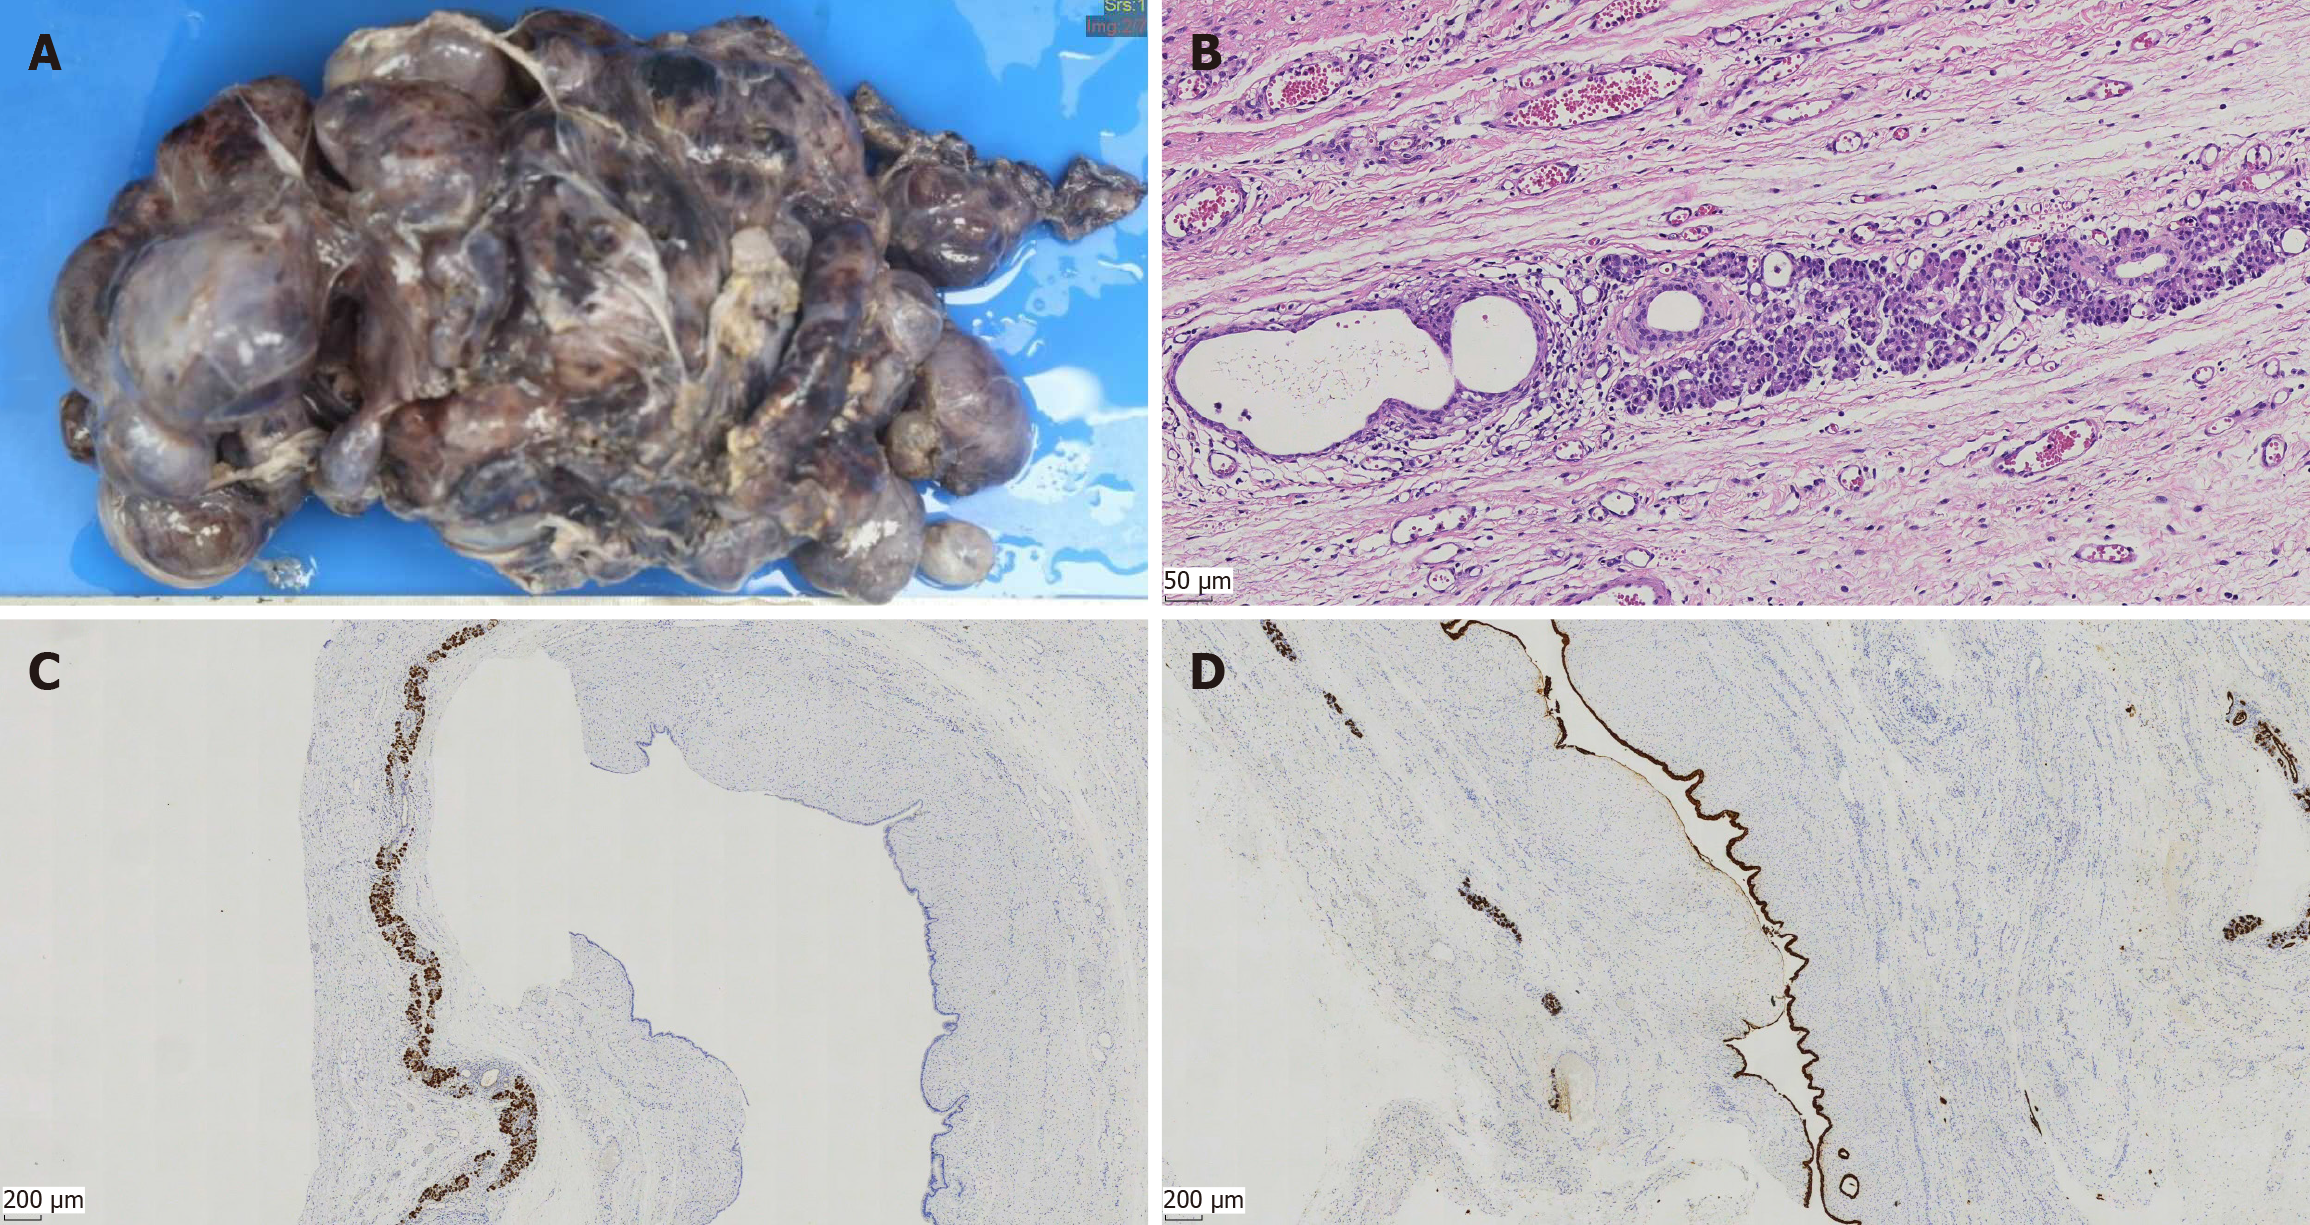

Figure 2 Gross morphology and microscopic images of resection specimen.

A: Gross morphology of resection specimen; B: Resection specimen consisting of multiple variable-sized cysts. The lesion is lined by cells with acinar differentiation, which have apical eosinophilic cytoplasmic granules and uniform nuclei. Cytologic atypia and mitotic figures are absent (hematoxylin and eosin, 200× magnification); C: Immunohistochemical positivity for the pancreatic enzyme trypsin is seen in the acinar cells (40× magnification); D: The lining cells are positive for CK19 and have strong and diffuse cytoplasmic staining for CK19 (40× magnification).